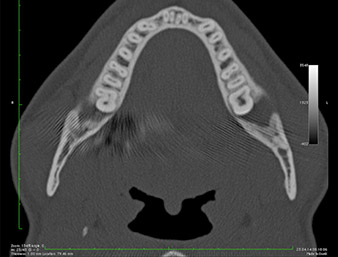

It could be seen in the 3D image (digital volume tomography) that the root remnant was located disto-caudally in the transition from the horizontal to the ascending portion of the mandible (Fig. 2).

DVT-image

Fig. 2: Transverse DVT image of the root remnant in the retromolar region.

Based on his medical history, our patient (non-smoker, 26 years old) had a very good chance of a successful outcome. Due to indication of the root remnant’s close proximity to the inferior alveolar nerve on the OPG, digital volume tomography was used in addition (6).